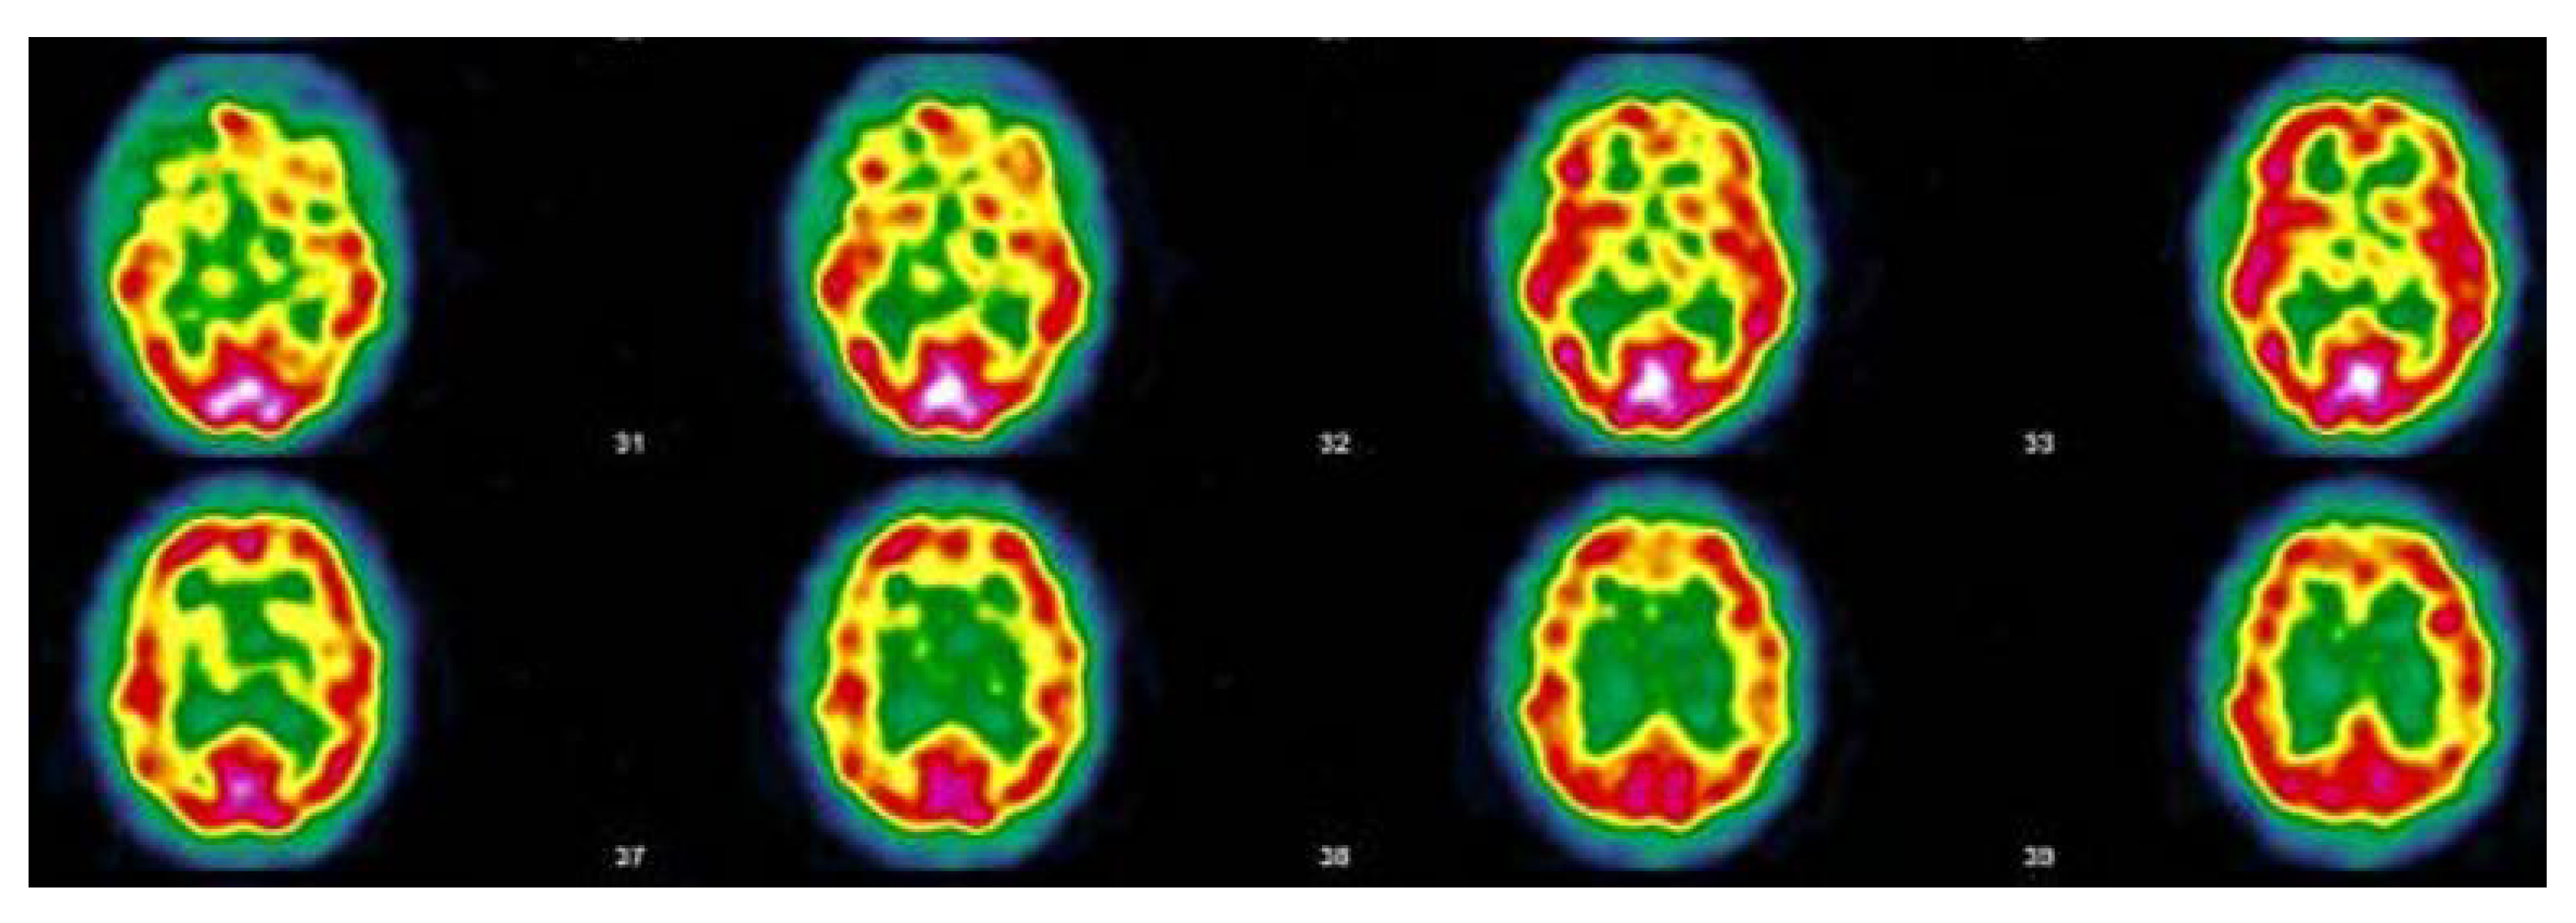

3.5. Narrative and SPECT-CT Images of Some Exemplary Cases

3.5.2. Patient MGA017

| 3 March 2021 Cough, aching, elevated temperature, headache, 20 days in bed, loss of taste, loss of smell, severe tinnitus, 20 days in total. Home care | 5 October 2021 Hearing loss in right ear, balance always disturbed, dizziness, loss of vision, quickly tired, severe weight gain, quickly out of breath, became depressed, pain in left hip every night, post-vaccinations headaches, memory loss, word retrieval deficit, repeats herself and doesn’t realize it, forgets which groceries she went to get, has trouble concentrating, disseminated myalgia, insomnia, loss of sense of direction | 17 November 2021 “Heterogeneous tracer distribution throughout the cortex, with more marked hypofixation in the bilateral predominantly left superior parietal, left parietal, bilateral medial temporal and bilateral predominantly right parieto-occipital areas. Diffuse subcortical periventricular hypofixation. The basal ganglia and cerebellum show preserved and symmetrical tracer uptake. Scintigraphic image suggestive of vascular damage in the broad sense.” |